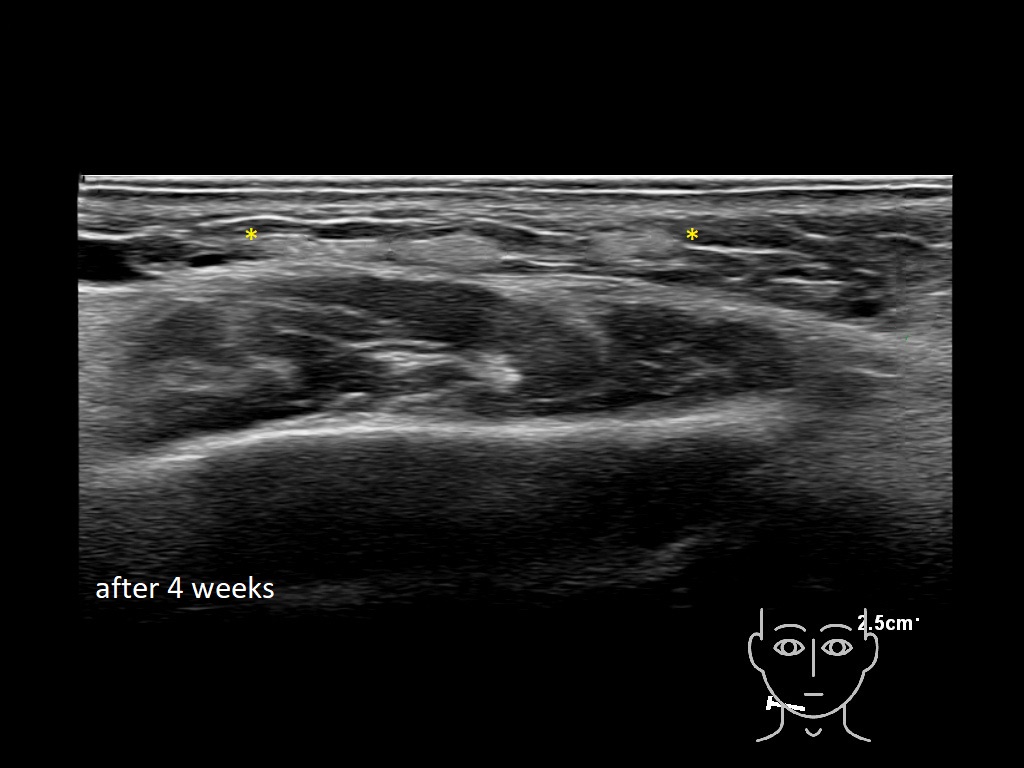

Fillers

Draw in the image on the right where the fillers are located. To check if your answer is correct, please click on the secondary image.

Fillers

Draw in the second image below where the fillers are located. To check if your answer is correct, swipe the first image to the right.